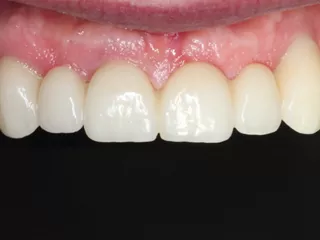

• Tissus mous au moment de la pose de la prothèse vissée définitive

• Restauration définitive au suivi à 6 mois